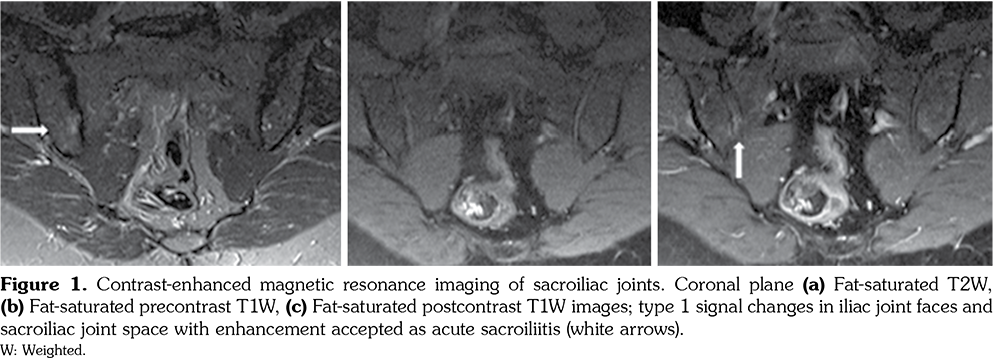

Magnetic resonance imaging (MRI) of SI joints was ordered in patients with IBP and normal conventional pelvic radiographs. MRI examination was performed with Siemens MAGNETOM Symphony 1.5 Tesla MRI devices (Siemens Medical Systems, Erlangen, Germany), 3 mm slice thickness. Intravenous administration of gadolinium (0.1 mL/kg dose) was used in all patients. Low signal intensity in T1 weighted (W) images and high signal intensity in T2W and fats at T2W images were accepted as edema and inflammation (type 1), high signal intensity in both T1W and T2W images and signal loss in fat-saturated T2W images were accepted as fatty degeneration (type 2), low signal intensity in both T1W and T2W images was accepted as sclerotic degenerative changes (type 2). Type 1 changes, enhancement after contrast application, and joint effusion were accepted as acute sacroiliitis, type 2 changes, narrowing or widening in SI joint space and irregularity in joint surface, subchondral bone resorption, ankylosis without type 1 changes or enhancement were accepted criteria for structural changes in MRI evaluation.

Conventional radiographic evaluation of SI joints was performed in all SLE patients with IBP and unilateral or bilateral grade 2 sacroiliitis was detected in six patients. MRI analysis of SI joints was obtained in 31 out of 40 (77.5%) SLE patients who had IBP, but not radiographic sacroiliitis. Bone marrow edema or contrast enhancement in SI joints (active sacroiliitis) were found in 14 patients, while sclerosis or fatty degeneration (structural changes) were revealed in two patients (Figures 1) in MRI. Good agreement was found by Cohen’s κ test between the radiologist and rheumatologist on radiological assessment (κ=0.80). Only one SLE patient with sacroiliitis was positive for HLA-B27 and she had a history of uveitis.